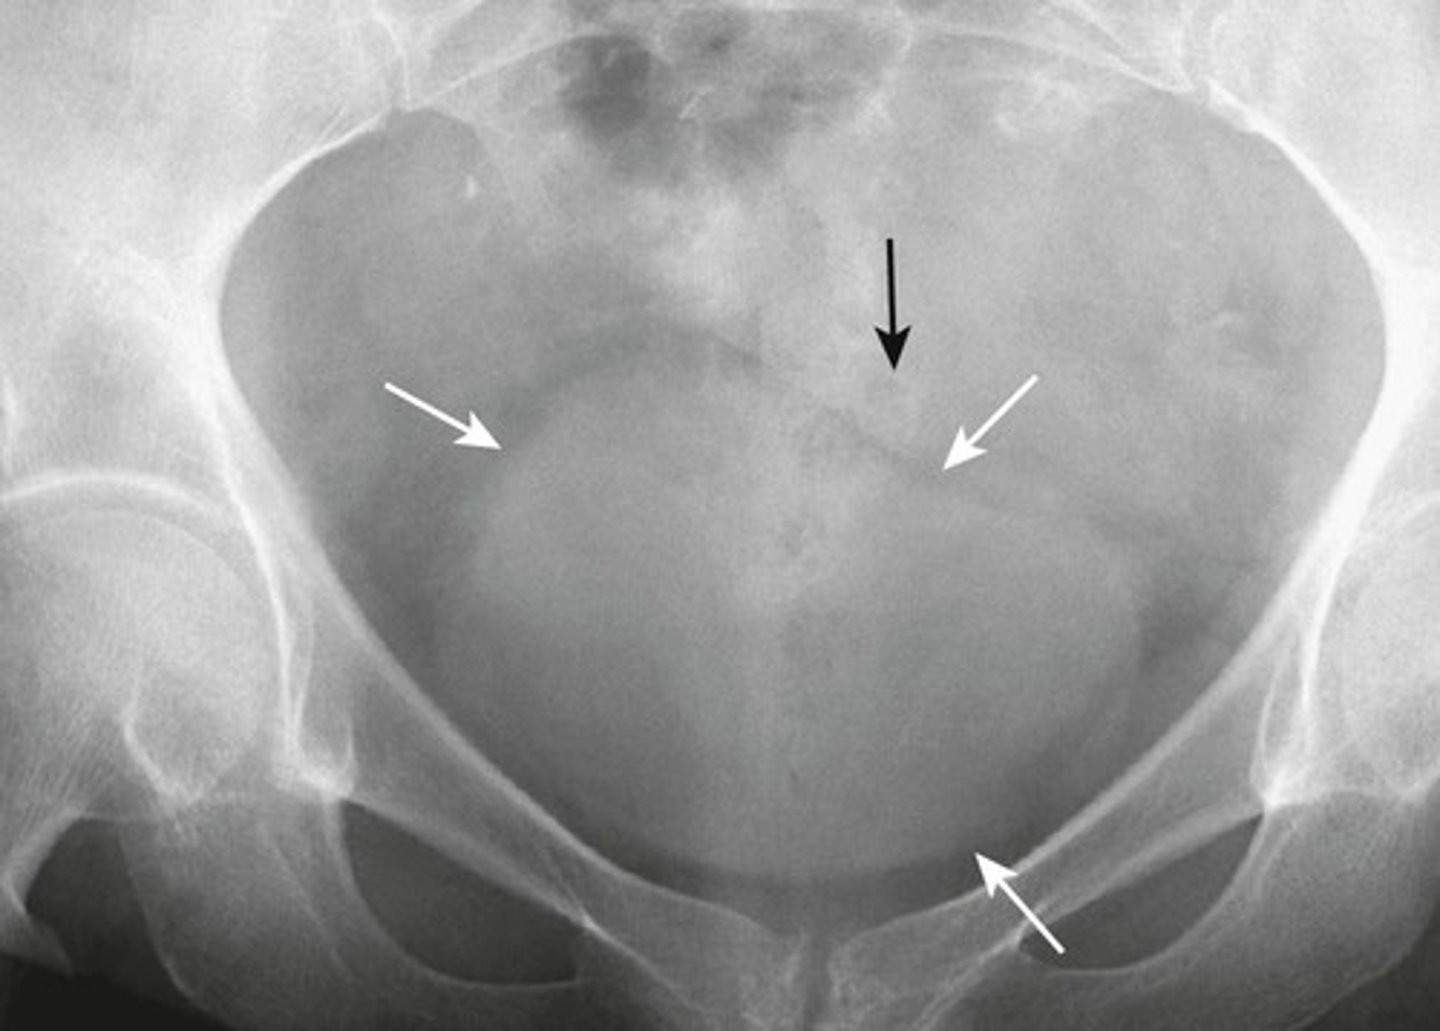

NORMAL BLADDER

WHITE ARROWS: outline of URINARY BLADDER visible by perivesical fat

BLACK ARROW: SIGMOID COLON occupying the space just above the bladder. (this is common in men; in women, soft tissue above bladder could be uterus or Sigmoid colon)